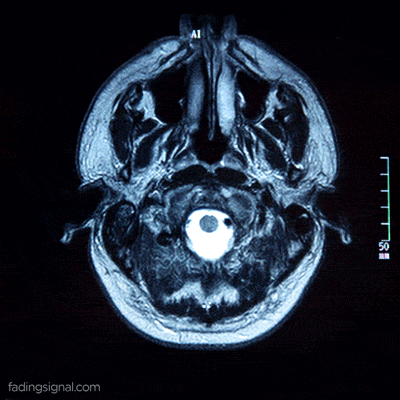

Até hoje, foram escritos rios de tinta sobre o órgão mais importante do corpo humano: o cérebro. Apesar disso, sua operação e todo o potencial que ele certamente tem ainda são um mistério para a ciência. Neste artigo, compartilharemos algumas curiosidades sobre o cérebro humano que você provavelmente não conhece.

Com o passar dos anos, as pesquisas científicas sobre este órgão fascinante avançam e desvendam todos os seus enigmas. A seguir, confira algumas dessas curiosidades que não o deixarão indiferente.

6 curiosidades sobre o cérebro humano que você certamente não conhece